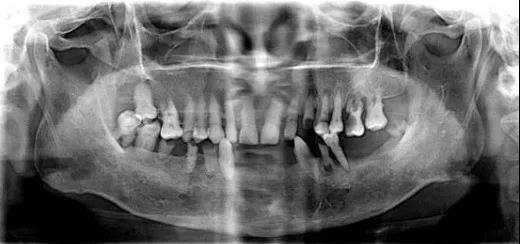

▲ 常见的牙片是二维的

医生可以从任意角度观察分析病例,如缺牙区牙槽骨吸收程度、余留牙是否有炎症等需要先进行治疗以避免干扰种植手术的问题。